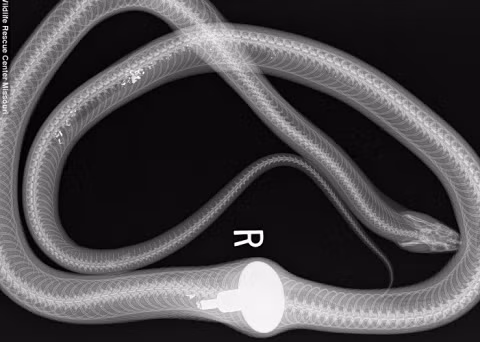

Con rắn chuột này lẻn vào đây để đánh cắp trứng, nhưng nó đã rơi vào kết cục thảm vì quá háu đói.

Con rắn trông thấy một vật tròn màu trắng cũ (tay nắm cửa) nằm ngổn ngang trên mặt đất, nó nhầm tưởng đó là một quả trứng nên vội vàng nuốt chửng.

Vật kim loại đã khiến con rắn đau đớn không thể bò đi nổi. Chủ nhà trông thấy đã gọi đến Trung tâm Cứu hộ động vật hoang dã. Nhờ đó con rắn được đưa tới bệnh viện điều trị.

Sau khi trải qua phẫu thuật lấy bỏ dị vật trong dạ dày ra, con rắn được điều trị phục hồi và được thả về với môi trường tự nhiên.